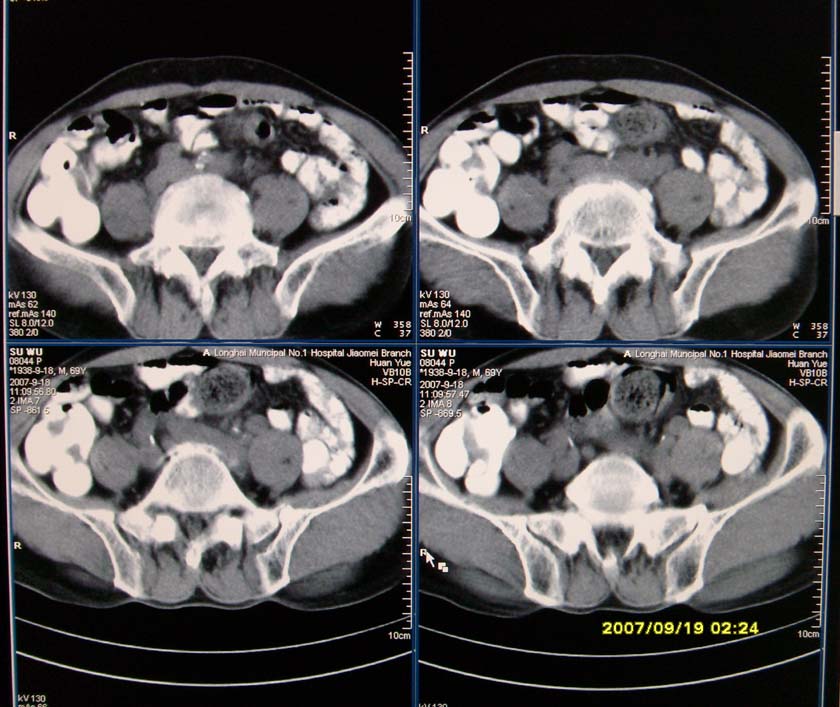

以下是引用xclzq_910在2007-9-19 16:58:00的发言:[br]直肠壁增厚,管腔偏移,直肠癌可能性大

以下是引用宝天曼在2007-9-19 21:11:00的发言:[br]根据直肠壁不规则增厚,考虑直肠肿瘤,不过最后的确诊还是需要肠镜.